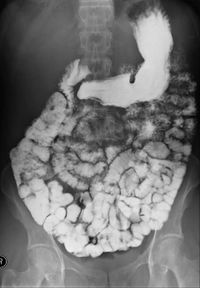

مركبات الباريوم (أيضاً من المواد المظللة الممتصة) ومثالها: سلفات الباريوم، والتي يتم حلها بالماء، ثم شربها، هذه المركبات لا تتحلل ولا يتم امتصاصها من قبل الأمعاء، مما يجعلها ملائمة لإظهار مجاري الجهاز الهضمي ومثالها ظاهر في الصورة. المواد المظللة من نوعية الباريوم تنشط حركة الأمعاء، هذه الخاصية تفسِّر استخدام هذه المواد أيضا كعلاج أو محاولة علاج الإنسداد المعوي، وهناك فائدة أخرى، وهي إمكان مراقبة نتائج هذه المحاولة العلاجية باستخدام الأشعة.